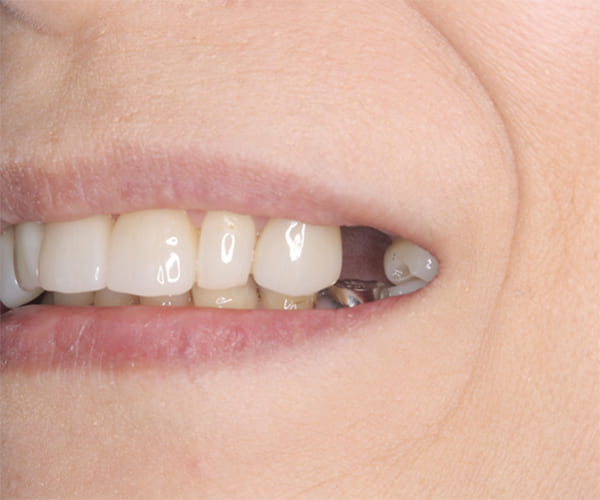

入れ歯が沈み込むことを防止するストッパーがない入れ歯を装着されていたため、お食事により入れ歯が沈み込みお痛みがでている状態でした。

笑った際に、太いバネが左右に見えるため、あまり大きく笑うことを避けていらっしゃいました。

作製した入れ歯は、お食事の際に入れ歯の沈み込みを予防するため、適切なストッパーを付与することで、入れ歯は沈み込まなくなり、お痛みは消失しました。

右下のバネの位置は後ろに、左下のバネは見えづらい形態のバネを用いる設計とすることで笑った際にバネが見えないようになり、気にされることはなくなられました。

裏側の見えない部分は金属を用いることで、お食事の際の入れ歯の動き、沈み込みを抑えお痛みがでづらく、入れ歯の動きが抑制されることで、長期的に残りの歯に負担のかかりにくい設計としました。